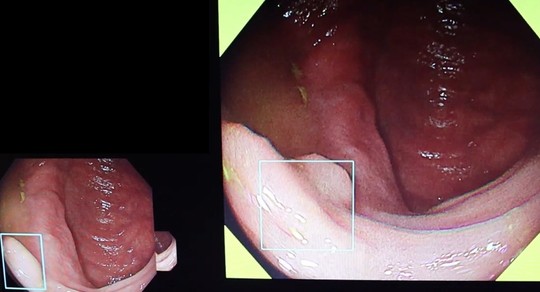

②反転観察でも確実に指摘

反転し観察も行います。AIも利用しますが、一番大切なのは経験豊富な内視鏡専門医がしっかり診断することです。